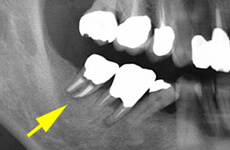

歯の移植・再植

根の先の病巣が大きいなど、状態が良くない歯の場合、根の治療のみでは治癒は期待できず、やむなく抜歯になってしまうケースがあります。 その場合、他の歯(例えば、親知らず)を抜いた部分に戻す移植法と、患歯を1度抜いて治療して戻す再植法があります。

感染してしまった部分をきれいにとり、清掃をして、きれいになったところで、細菌が増えないように薬をつめます。

■移植法

■再植法